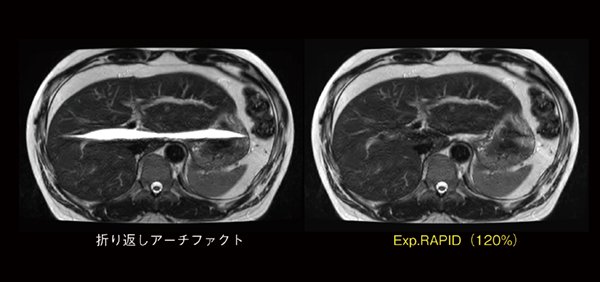

また,撮像視野(FOV)内に被写体が含まれておらず,位相方向にオーバーサンプリングをしていない場合,折り返しアーチファクトとして偽像が生じることがあります。このような場合には,撮像後の折り返しアーチファクト画像に対し,「Exp.RAPID(エキスパンド ラピッド)」のパーセンテージを変更することにより,折り返しアーチファクトの偽像部分を展開します。図4に,肝臓レベルの位置で皮下脂肪信号の折り返しアーチファクトが生じた画像を示しますが,Exp.RAPIDで画像再構成した画像では,折り返しアーチファクトの偽像部分が低減されていることがわかります。

図4 Exp.RAPID画像再構成による折り返しアーチファクト低減効果

折り返しアーチファクト像(左)では,画像中央に皮下脂肪信号の偽像があるが, Exp.RAPIDを120%に設定した再構成画像(右)では,折り返しアーチファクトの偽像部分がなくなっていることがわかる。